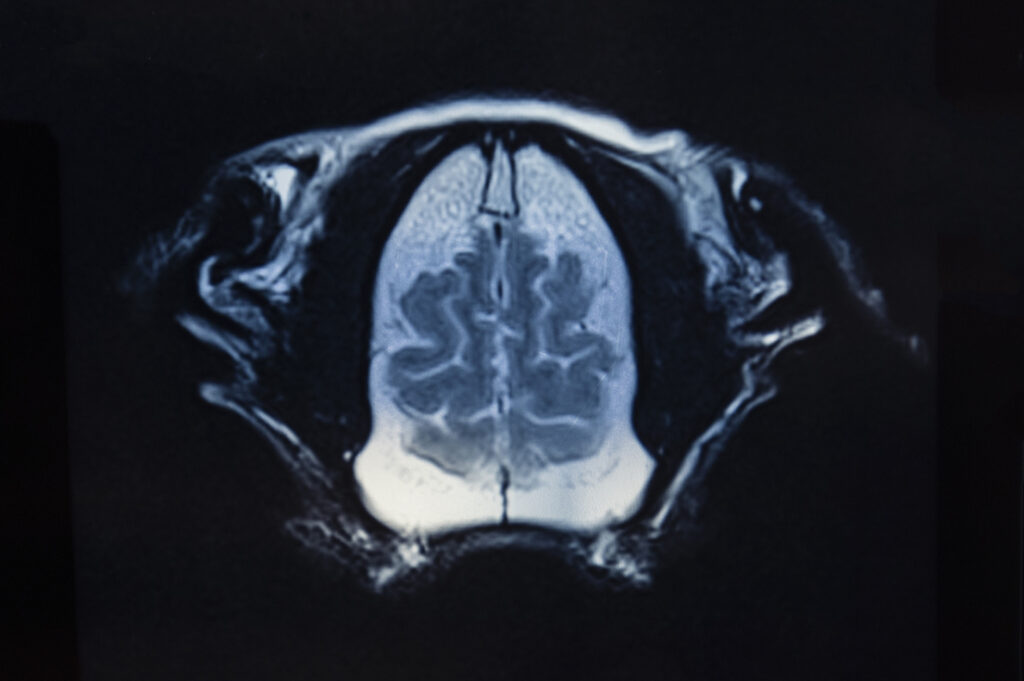

Le Centre vétérinaire Univet Wavre Beumont est équipé d’une IRM (Imagerie par Résonance Magnétique), une technologie avancée permettant de visualiser avec une grande précision les organes et les tissus de votre animal.

L’IRM est une technique d’imagerie médicale avancée qui permet d’observer avec précision les tissus mous : cerveau, moelle épinière, muscles, ligaments ou encore organes internes.

Contrairement à la radiographie ou au scanner, elle permet de visualiser des structures invisibles autrement, avec un niveau de détail particulièrement élevé.

- analyser le cerveau et le système nerveux

- détecter des lésions invisibles aux autres examens